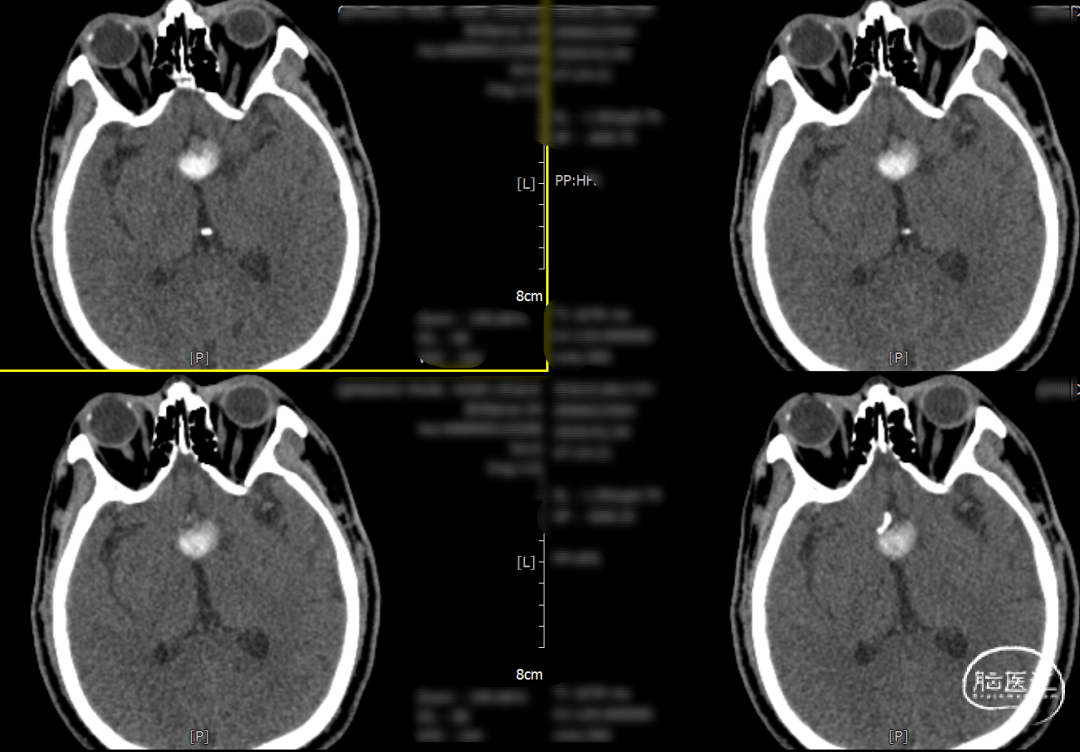

术后一天检查。